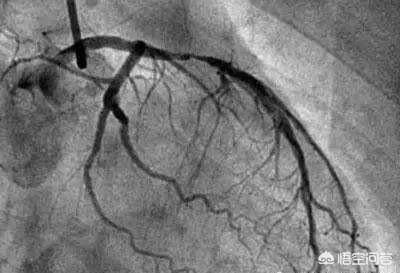

L'imagerie cardiaque que vous avez mentionnée, qui représente la plus grande proportion, est l'étalon-or utilisé pour diagnostiquer la maladie coronarienne - la coronarographie. Ces dernières années, l'incidence de la maladie coronarienne dans notre pays est de plus en plus élevée, et les jeunes sont de plus en plus nombreux. Dans les hôpitaux provinciaux et municipaux de médecine interne cardiovasculaire, la coronarographie est un repas courant, et même dans certains hôpitaux de comté, un grand nombre de coronarographies et de thérapies interventionnelles coronariennes sont également pratiquées. Les médecins et les patients sont habitués à la coronarographie. En fin de compte, quels sont les effets néfastes sur l'organisme ? Nous allons ensemble comprendre comment faire une coronarographie ? Quels sont les dangers ? Quelles sont les solutions ?

- Les produits de contraste "éclairent" les artères coronaires :Les artères coronaires du corps humain sont relativement petites : le tronc principal des artères coronaires ne mesure que cinq ou six millimètres, certaines des branches les plus importantes mesurent environ deux ou trois millimètres, et les autres sont des branches encore plus petites ; ces vaisseaux sanguins sont reliés aux tissus environnants et sont recouverts par les os, les muscles, etc. devant eux. Lors de la coronarographie, un agent de contraste est injecté à l'intérieur du cathéter mentionné plus haut afin de remplir les artères coronaires d'agent de contraste.L'agent de contraste est un médicament imperméable aux rayons X qui "illumine" les artères coronaires pendant la coronarographie afin que nous puissions voir clairement la distribution, la taille et la présence de sténoses et d'obstructions dans les artères coronaires.

- La DSA (Digital Subtraction Angiography) est une caméra pour les vaisseaux sanguins :L'équipement utilisé pour prendre des photos des artères coronaires mentionné plus haut est le DSA, qui est en fait également une forme d'examen aux rayons X, capable de prendre des photos et d'enregistrer des vidéos des différentes artères coronaires sous de multiples angles tout en injectant le produit de contraste, ce qui peut être considéré comme un angle de 360 degrés sans issue, et ces photos et vidéos peuvent être déposées sur un CD-ROM pour être facilement conservées et analysées.C'est parce que la coronarographie permet d'obtenir des photographies et des vidéos d'une telle clarté que la coronarographie est l'étalon-or du diagnostic de la maladie coronarienne.

La coronarographie consiste à enfiler une aiguille dans l'artère fémorale, à envoyer un tube jusqu'à l'emplacement de l'artère coronaire, à appliquer un produit de contraste iodé et à montrer l'artère coronaire, ce qui permet de diagnostiquer les maladies congénitales de l'artère coronaire, l'athérosclérose, les anévrismes, les malformations artérielles et d'autres maladies, dont la plupart sont des athéroscléroses qui entraînent un rétrécissement de la lumière. Le degré de sténose peut être évalué et, dans le cas d'une sténose grave, avec infarctus du myocarde, un stent peut être directement mis en place pour ouvrir la lumière rétrécie et rétablir le flux sanguin à des fins thérapeutiques.

La cardiographie fait référence à l'angiographie coronarienne. Le processus général consiste à pratiquer une petite ouverture dans l'artère radiale ou fémorale du premier examinateur, à insérer un fin cathéter à partir de l'incision, à suivre la direction de l'artère, à pénétrer profondément dans l'artère coronaire, puis à injecter un produit de contraste, de sorte que l'imagerie de l'artère coronaire puisse être claire sur la maladie coronarienne et ses branches, sur le rétrécissement du site et sur le degré de la maladie coronarienne, ce qui permet de diagnostiquer la maladie coronarienne. "l'étalon-or". Ci-dessous, nous abordons ensemble trois questions :